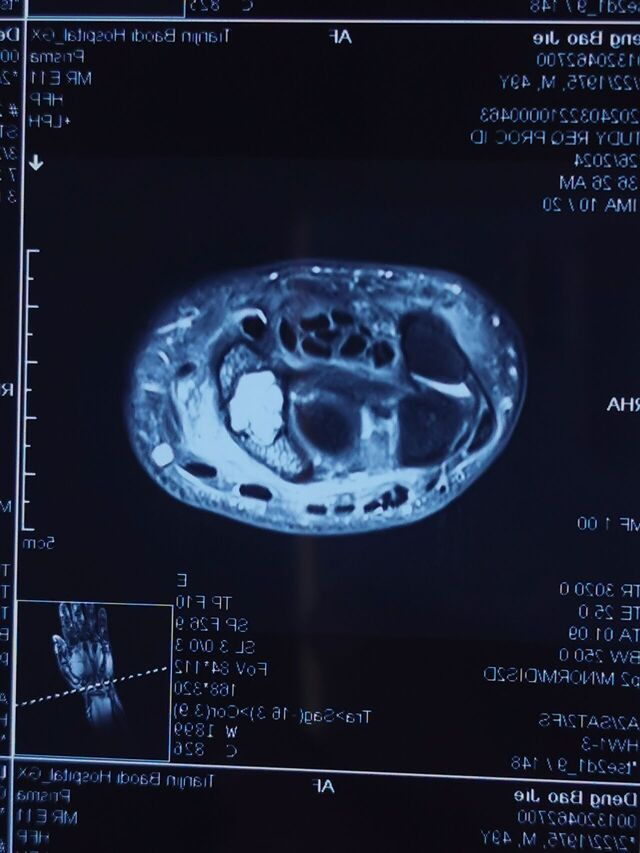

今天上午特需门诊的病例

特需门诊隔壁就是放射二科办公室

拿着片子向放射二科老师请教

内生软骨瘤和骨囊肿的影像学区别

这种骨囊肿,更接近于骨坏死早期表现

而内生软骨瘤表现为多个颗粒状影像

这个治疗应该按照舟骨不愈合的标准做